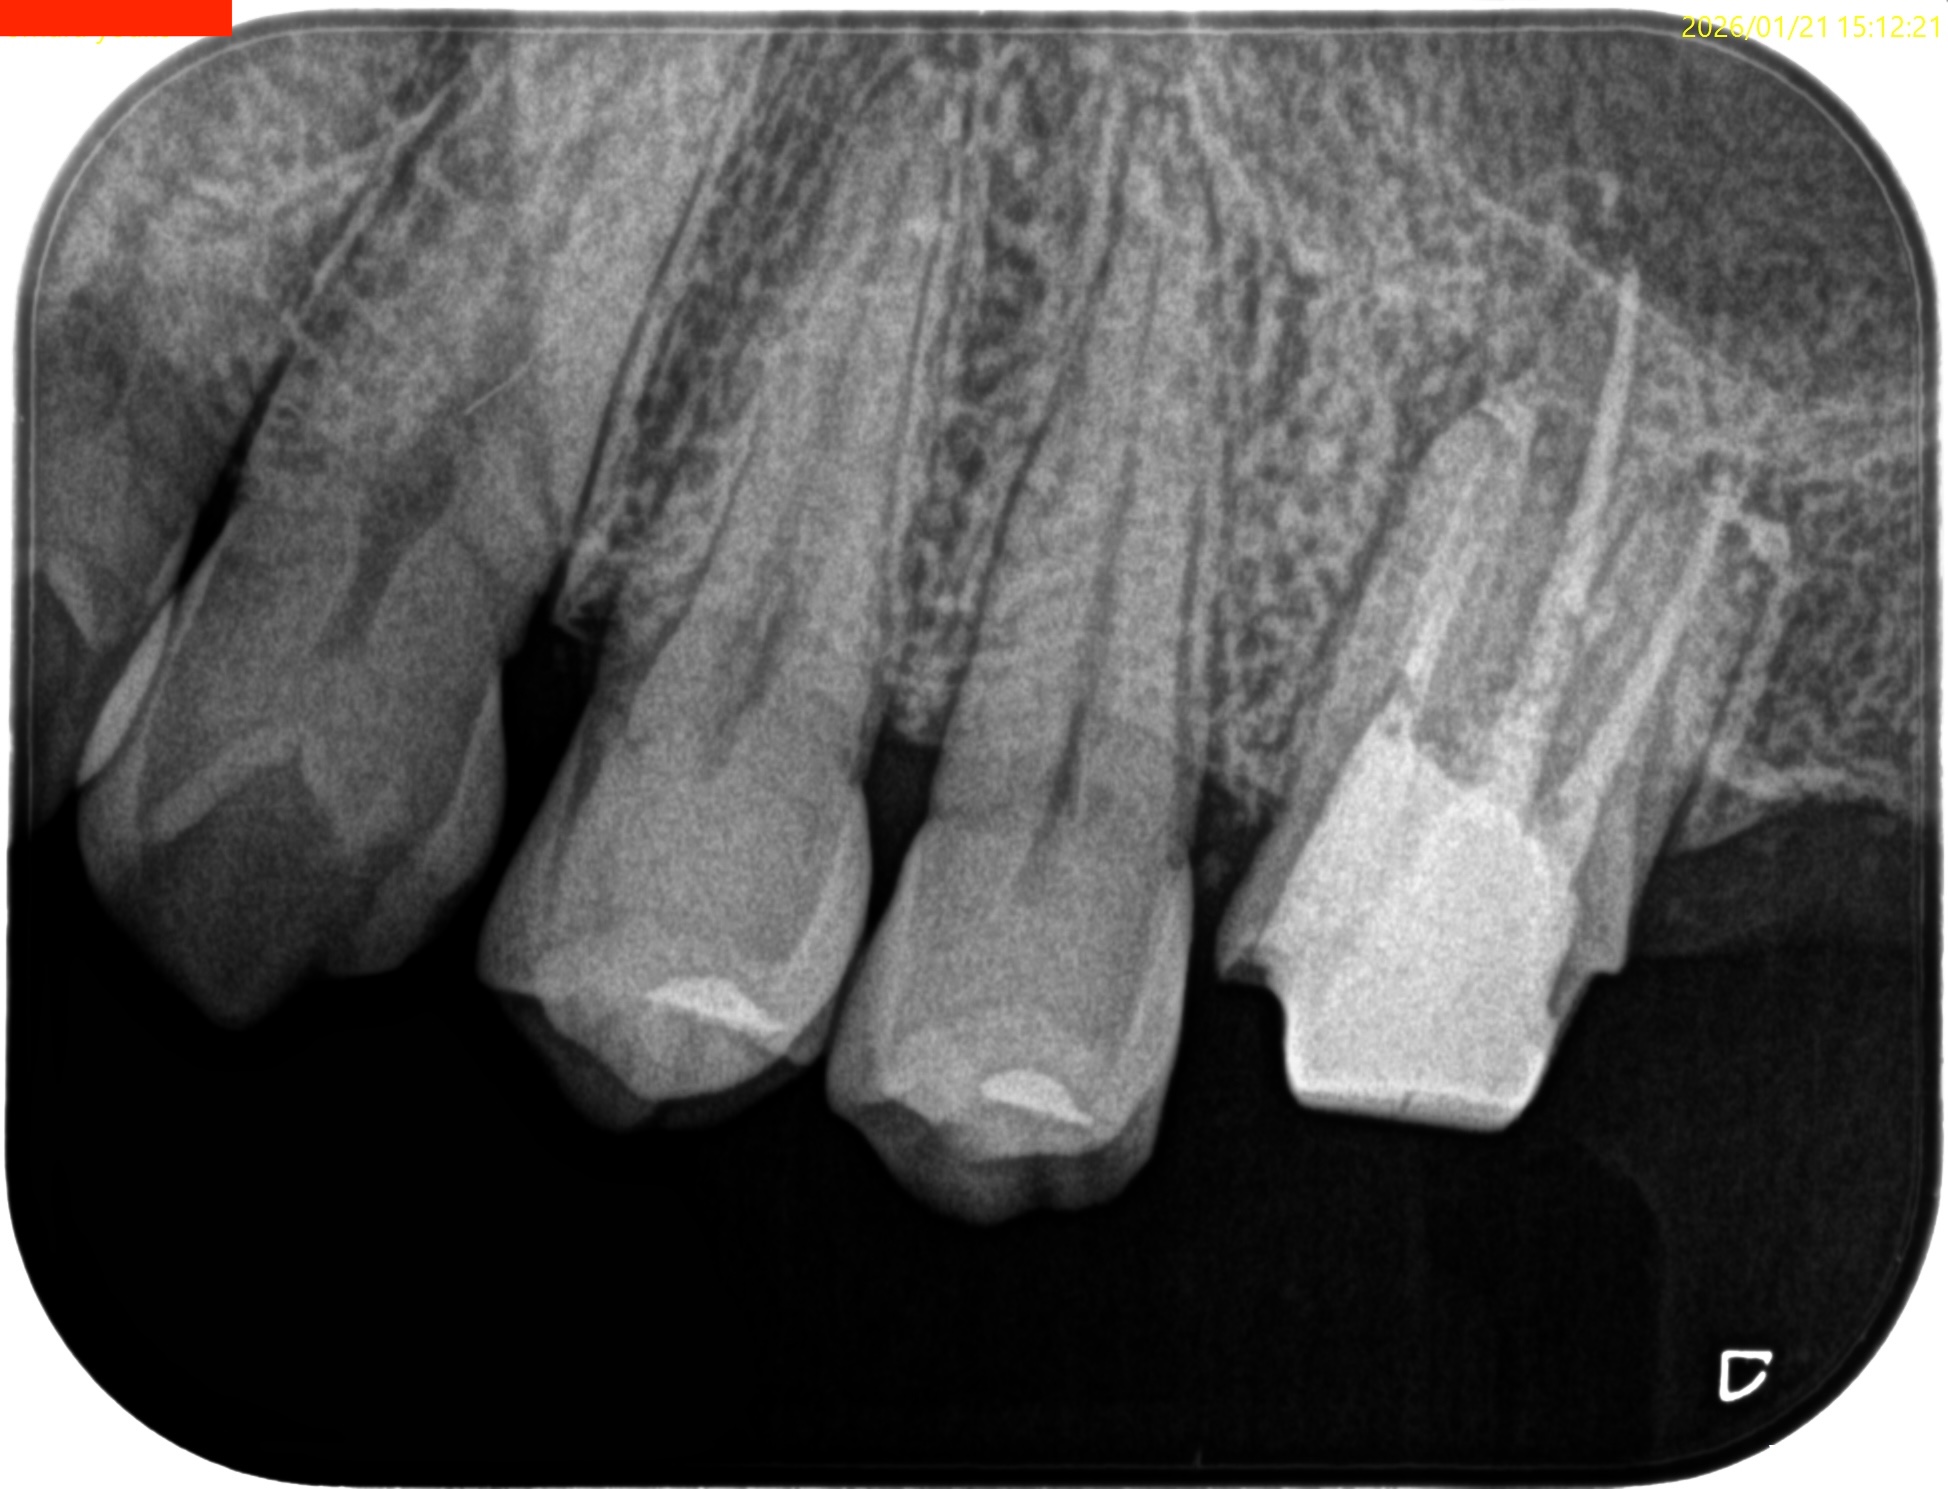

#14 RCT 2yr recall(2026.1.21)

MB1

MB2

DB

P

MB,DBの根尖部に病変が残存している。

臨床検査での咬合痛が生活に支障があるそうだ。